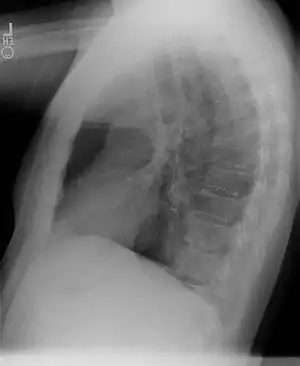

Chest radiograph

- Sequestrations typically appear as a uniformly dense mass within the thoracic cavity or pulmonary parenchyma.

- Recurrent infection can lead to the development of cystic areas within the mass.

- Air-fluid levels due to bronchial communication can be seen.